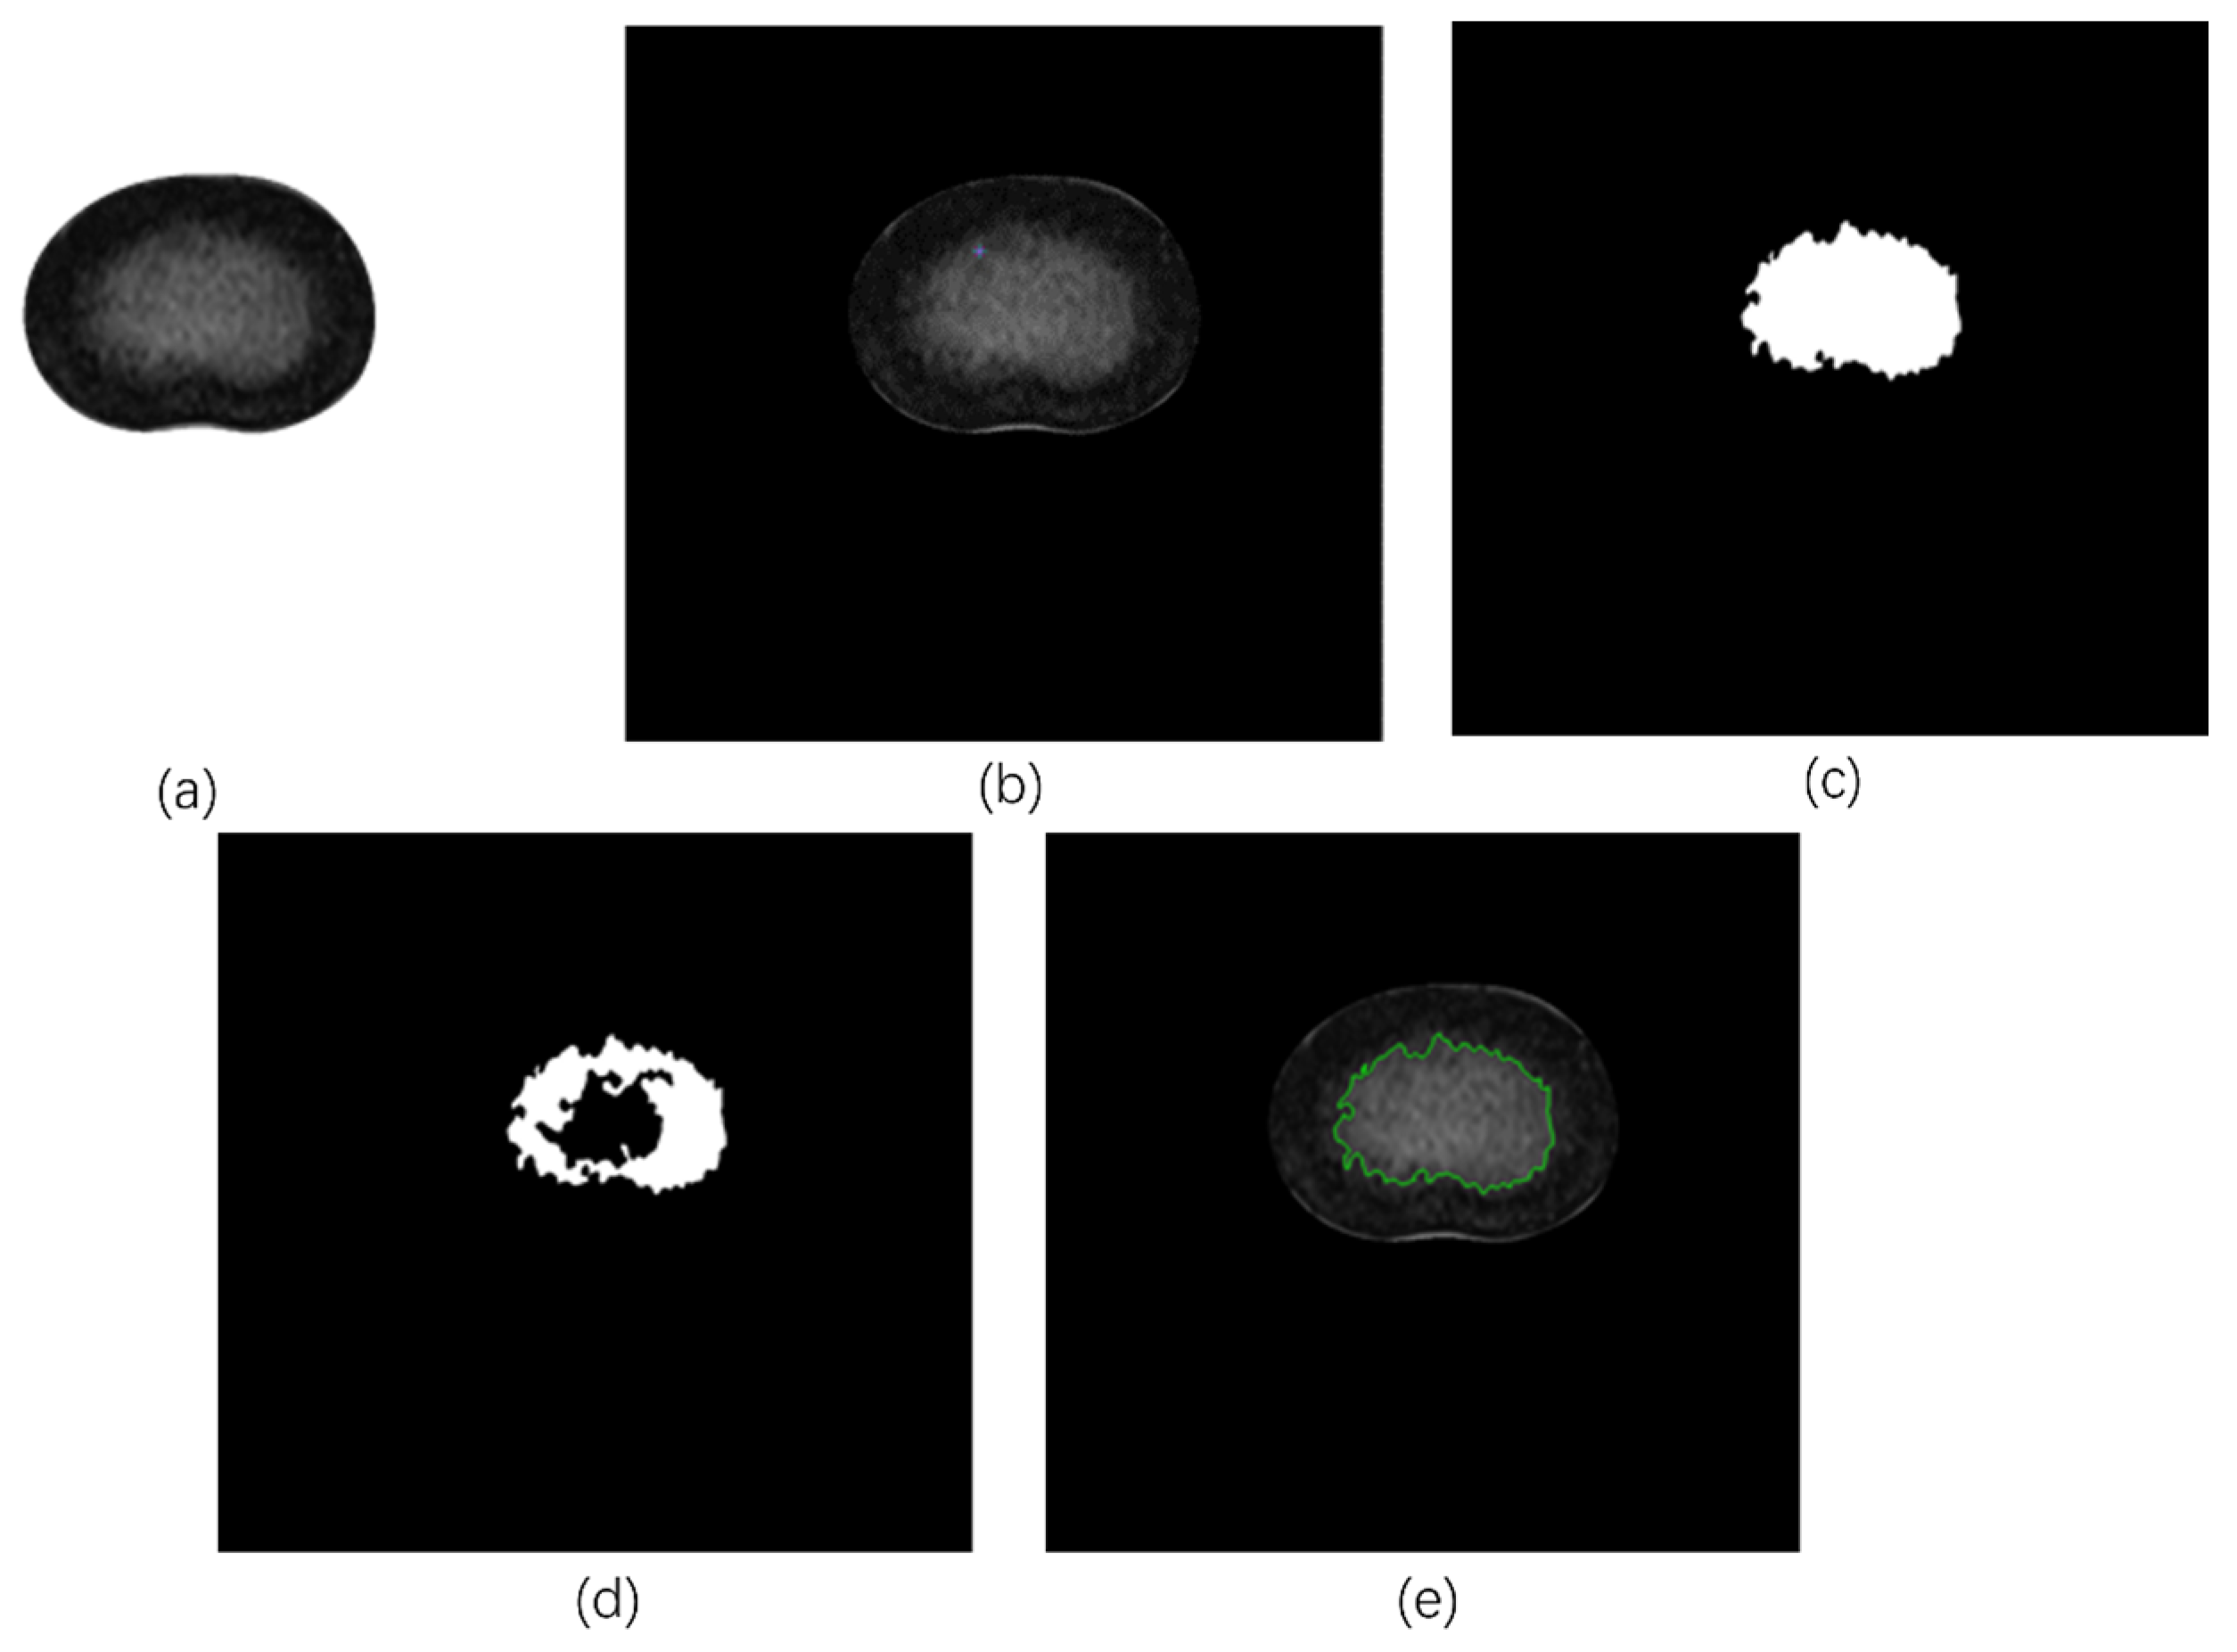

2.2.2. Tracing the NP Contours

- Fuzzy C-means algorithm (FCM)

- Region growing algorithm (RG)

- Perform expansion corrosion and opening–closing operations on the obtained region, draw the outline of the obtained mask, and complete the extraction of the NP region.

- Manual tracing (MT)